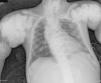

The chest X-ray (Fig. 1) demonstrated nodular periarticular calcification in the shoulders, dorsal vertebral osteosclerosis and vertebral collapse of thoracic vertebrae 5 and 6, with sequelae of rib fractures and a fracture of the right humerus. An abdominal X-ray (Fig. 2) showed bilateral nephrocalcinosis, vertebral osteosclerosis which also affected pelvic bones, bilateral nodular calcifications and a subtrochanteric fracture.

Nodular calcifications of the shoulders. Superior and inferior vertebral plate osteosclerosis (rugby jersey spine) and vertebral collapse of dorsal vertebrae 5 and 6. Bulbous growth on the ends of the ribs and clavicles. Osteosclerosis of clavicles and rib fracture sequelae. Fracture of the right humerus.